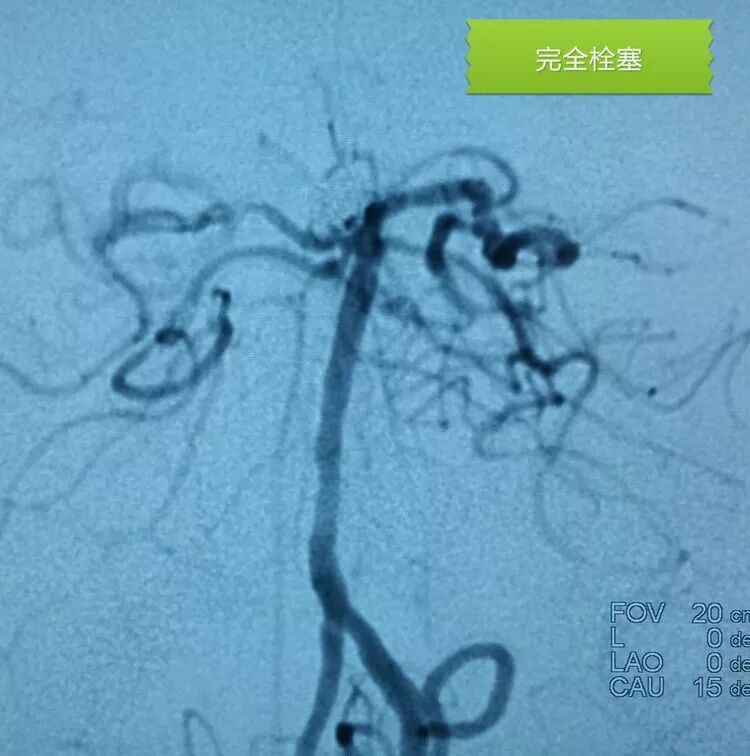

扁平状的前交通动脉瘤

仍然用双微管技术栓塞,一根直头微导管进入瘤体上部,另一根微导管头端塑成C形进入瘤体下部,分区栓塞该瘤